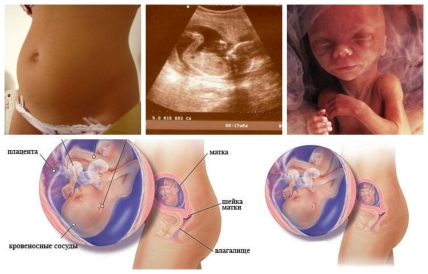

17 неделя беременности: завершилось формирование плаценты, ее пронизывает густая сеть кровеносных сосудов. По сосудам малышу доставляются питательные вещества и кислород, выводятся продукты переработки. Сейчас вес плаценты около 480 грамм, а толщина 2.5 см.

Матка продолжает расти, раздвигая внутренние органы, и уже почти достигла уровня печени. Дно матки приняло сферическую форму, а сама она вытянулась. На этом сроке матка находится на 3-5 см.ниже пупка.

На 17 неделе беременности малыш продолжает расти: его рост около 13 см. и вес около 120 г., его тело покрыто тонкой кожицей, а процент жира составляет 0,5% от общей массы тела. Вскоре у малыша начнет образовываться подкожно-жировая клетчатка – особый вид ткани для осуществления теплообмена в организме, и к родам количество подкожного жира составит около 60-70%.

Но сохранить необходимую температуру тела малышу необходимо и в утробе матери, для этого на его коже появляется специальный пушок – лануго. Этот волосяной пушок задерживает восковидное вещество, которое выделяет детский организм, образуя плотную смазку. Помимо сохранения температуры тела эта смазка поможет ребенку максимально легко проходить по родовым путям.

Ручки малыша полноценно сгибаются в локтевых суставах, а пальчики большую часть времени сжаты в кулачки и лишь иногда распрямляются. К 17 неделе беременности уже полностью сформирован орган слуха, теперь малыш хорошо слышит. Звуки окружают его: ребенок слышит сердцебиение матери, звуки работы кишечника, шум ее дыхания, гул тока крови в сосудах, может слышать различные звуки извне, включая мамин голос.

Молочные зубки ребенка в этот период покрываются дентином, а под ними закладываются постоянные зубы. Также к 17 неделе беременности завершается образование проводящей системы сердца. Теперь оно может работать автономно, то есть независимо от сигналов головного мозга.

В конце недели плод имеет длину 13 см и весит в среднем 130-150 г.

Во времяУЗИ на 17 неделе беременности будущая мама уже сможет узнать пол своего малыша при условии что, что он не повернется к экрану спинкой. Также врач проверит, соответствуют ли размеры малыша и матки срокам беременности, нет ли аномалий в развитии, какое сердцебиение плода, двигательная активность, в каком состоянии маточный миометрий и околоплодные воды.